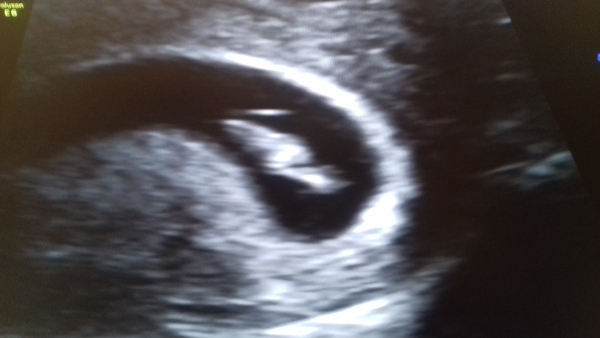

reginafalange2020 · 27/01/2020 18:50

7 weeks 4 days internal scan